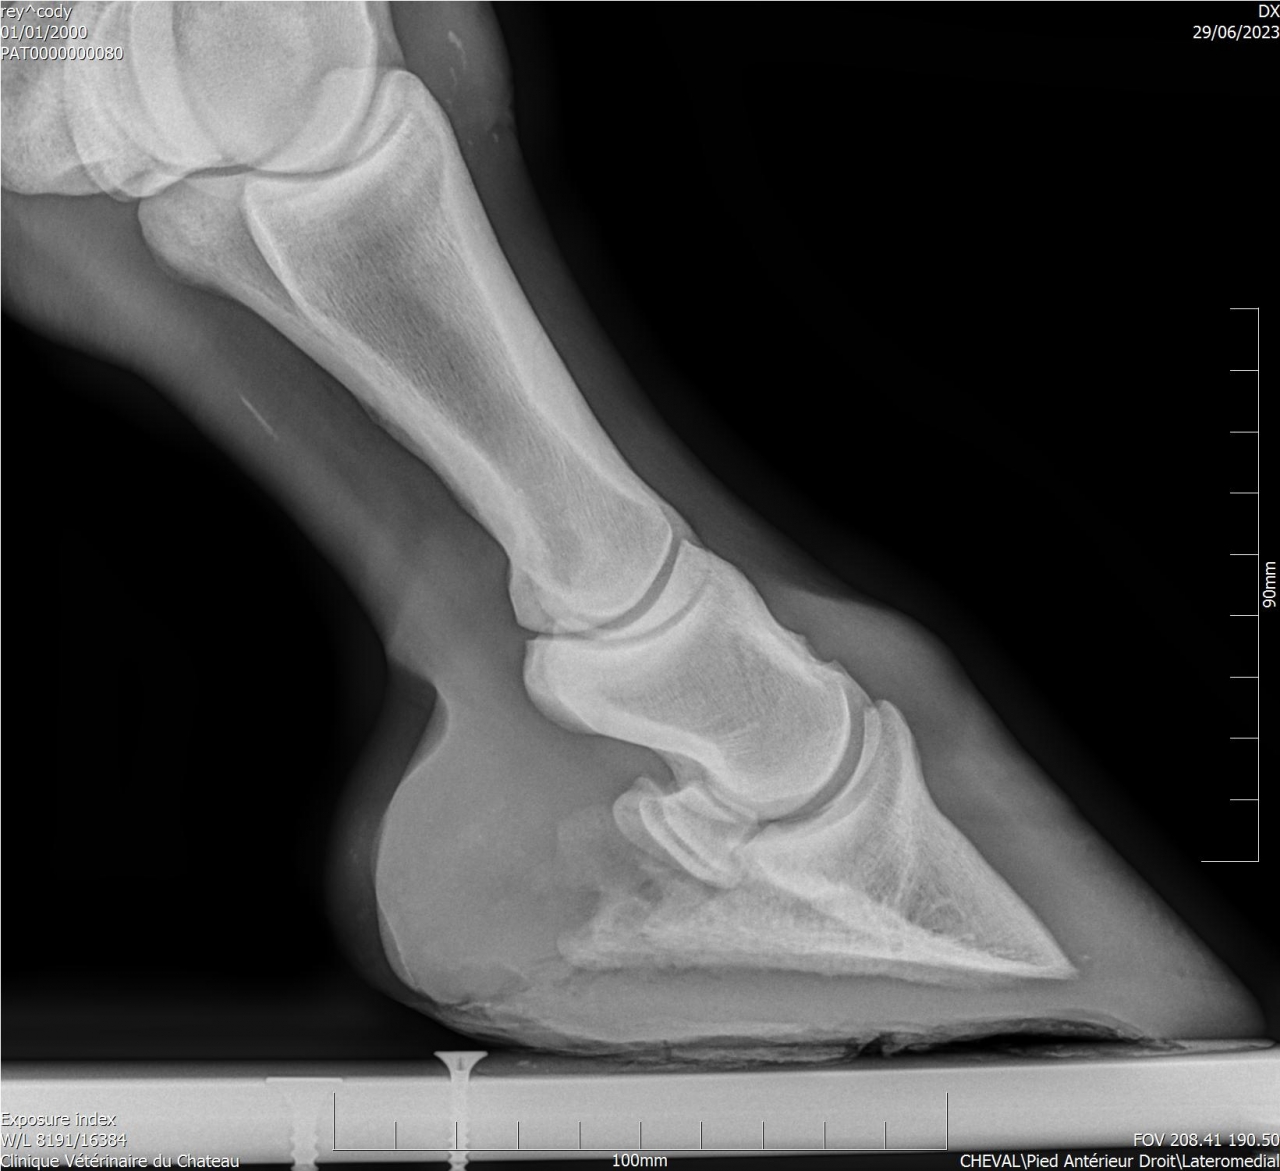

| Dire merci | Je suppose très fortement que les vibrations sont douloureuses. J’ai même dû le faire tranquiliser lors de l'avant dernier ferrage. La dernière fois avec les anti inflammatoires (inflacam) ça s’était bien passé. Mardi j’ai donné du rheumoxidil mais je ne l’ai donné qu’une heure avant au lieu de 2 ... Cody a une ossification des processus palmaires aux 2 antérieurs. Il est trop sensible pieds nus sur sol dur (même au pré) que j’ai dû me résoudre à le ferrer. J’ai testé les hipposandales et ça n’a rien changé. Il est beaucoup mieux avec ce "nouveau" maréchal ferrant qui met des fers en aluminium avec plaques en cuir. Le précédent faisait une ferrure oignon et aucune différence flagrante avec pieds nus. |

Par goss_de_panloup : le 02/11/24 à 20:39:15

| Dire merci | Aucun des vétos consultés n’a été capable de donner une explication à la boiterie et à la douleur au ferrage ... Voici des radios de l’année dernière : ![]() ![]() Si quelqu'un a une bonne adresse de spécialiste en Isère je prends. |

| Dire merci | Tu as une radio LM par hasard ? |

| Dire merci | Un cheval qui bosse pas, qui a juste 10 ans et qui a une locomotion dégradée selon les jours, ça pue l arthrose précoce, le naviculaire ou chais pas quoi. Il te faut un vrai bilan ds une clinique qui sait faire les radios et échos et qui sait les lire |